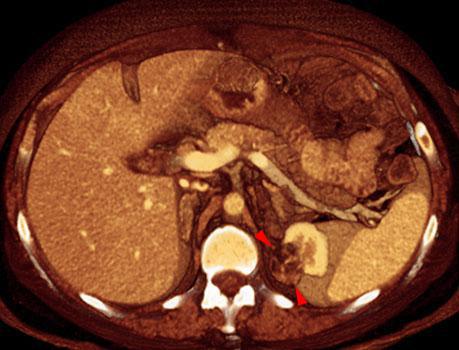

Angiomiolipoma renal 1

VR seccional. Visión axial caudal. TC contrastado en fase venosa que muestra una lesión cortical en el polo renal superior izquierdo (puntas de flecha) heterogénea, con contenido graso, confirmando este diagnóstico